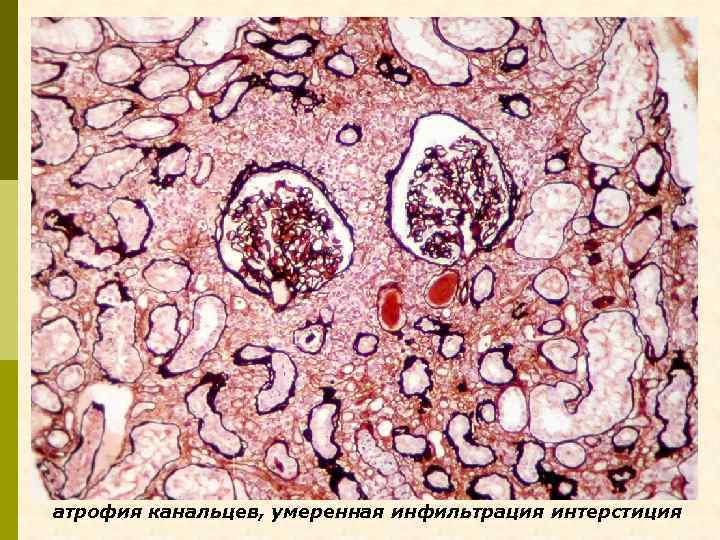

атрофия канальцев, умеренная инфильтрация интерстиция

Ig. A +++ Ig. G ++ Заключение: Ig. A-нефропатия, III класс (по M. Haas): незначительная мезангиальная пролиферация с сегментарным гломерулосклерозом (12%), полулуниями (6%), умеренной атрофией канальцев, диффузно-очаговым острым канальцевым некрозом и диффузно-очаговым тубуло-интерстициальным воспалением.